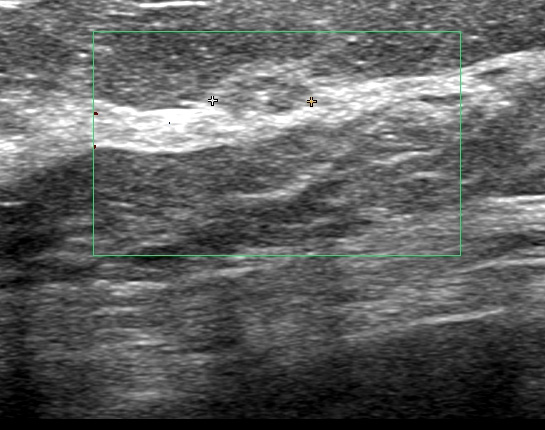

これは(上から)大胸筋、小胸筋、(黄色いのが)リンパ節、その下に「腋窩静脈」

この状態での細胞診

このリンパ節は「6mm」

このように(細胞診の)針を大胸筋を貫き、(更に)小胸筋を貫き漸く「リンパ節(たった6mm)」に達する

ただし、針が浅いと「細胞量不足」となり、深いと「腋窩静脈穿刺=出血!」となる究極の状態

結果、無事に「クラスⅤ(私は癌ならⅤしか出しません。)」

★この細胞診は私を、間違いなく更なる高みへと向かわせたのです。